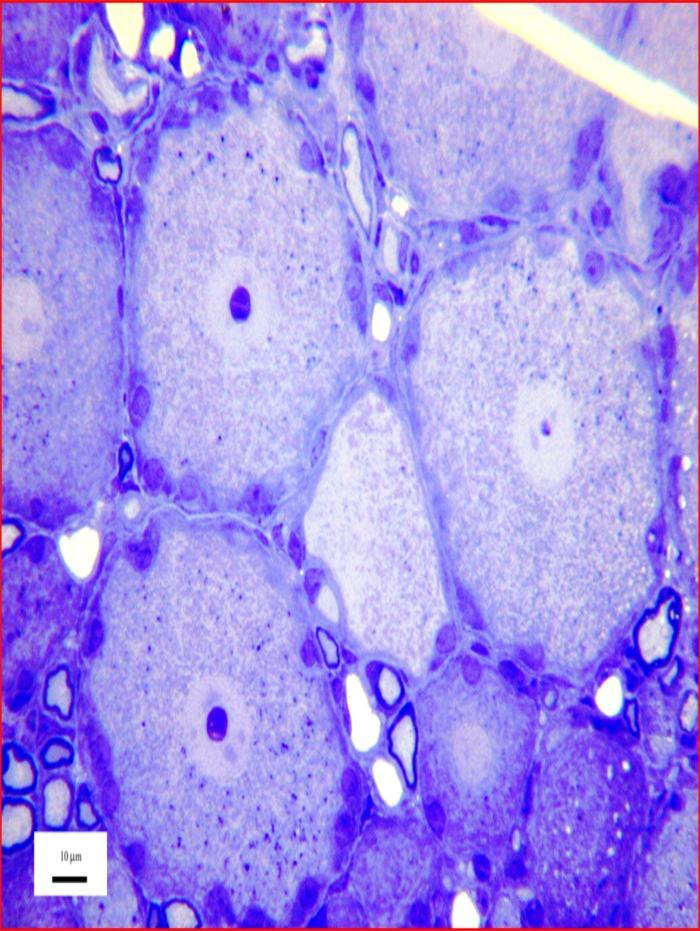

Image above: Microscopy image of Sensory nerve cells, courtesy of Dr R W Banks.

Sensory nerve cells

Sensory nerve cells such as these are located in a swelling, or ganglion, on the dorsal root of a nerve connected to the spinal cord. Each gives rise to a single nerve fibre, or axon, that branches once within the ganglion. One branch enters the spinal cord to make connexions with other nerve cells, while the other passes through peripheral nerves to form a sensory ending in skin, muscle, joints, viscera, etc. The endings are usually specialised to respond variously to touch, pressure, movement, heat, etc. The tissue has been chemically fixed, dehydrated, and embedded in epoxy resin. The section was cut with a glass knife and is 1 micrometre thick. It was stained with toluidine blue for light microscopy.